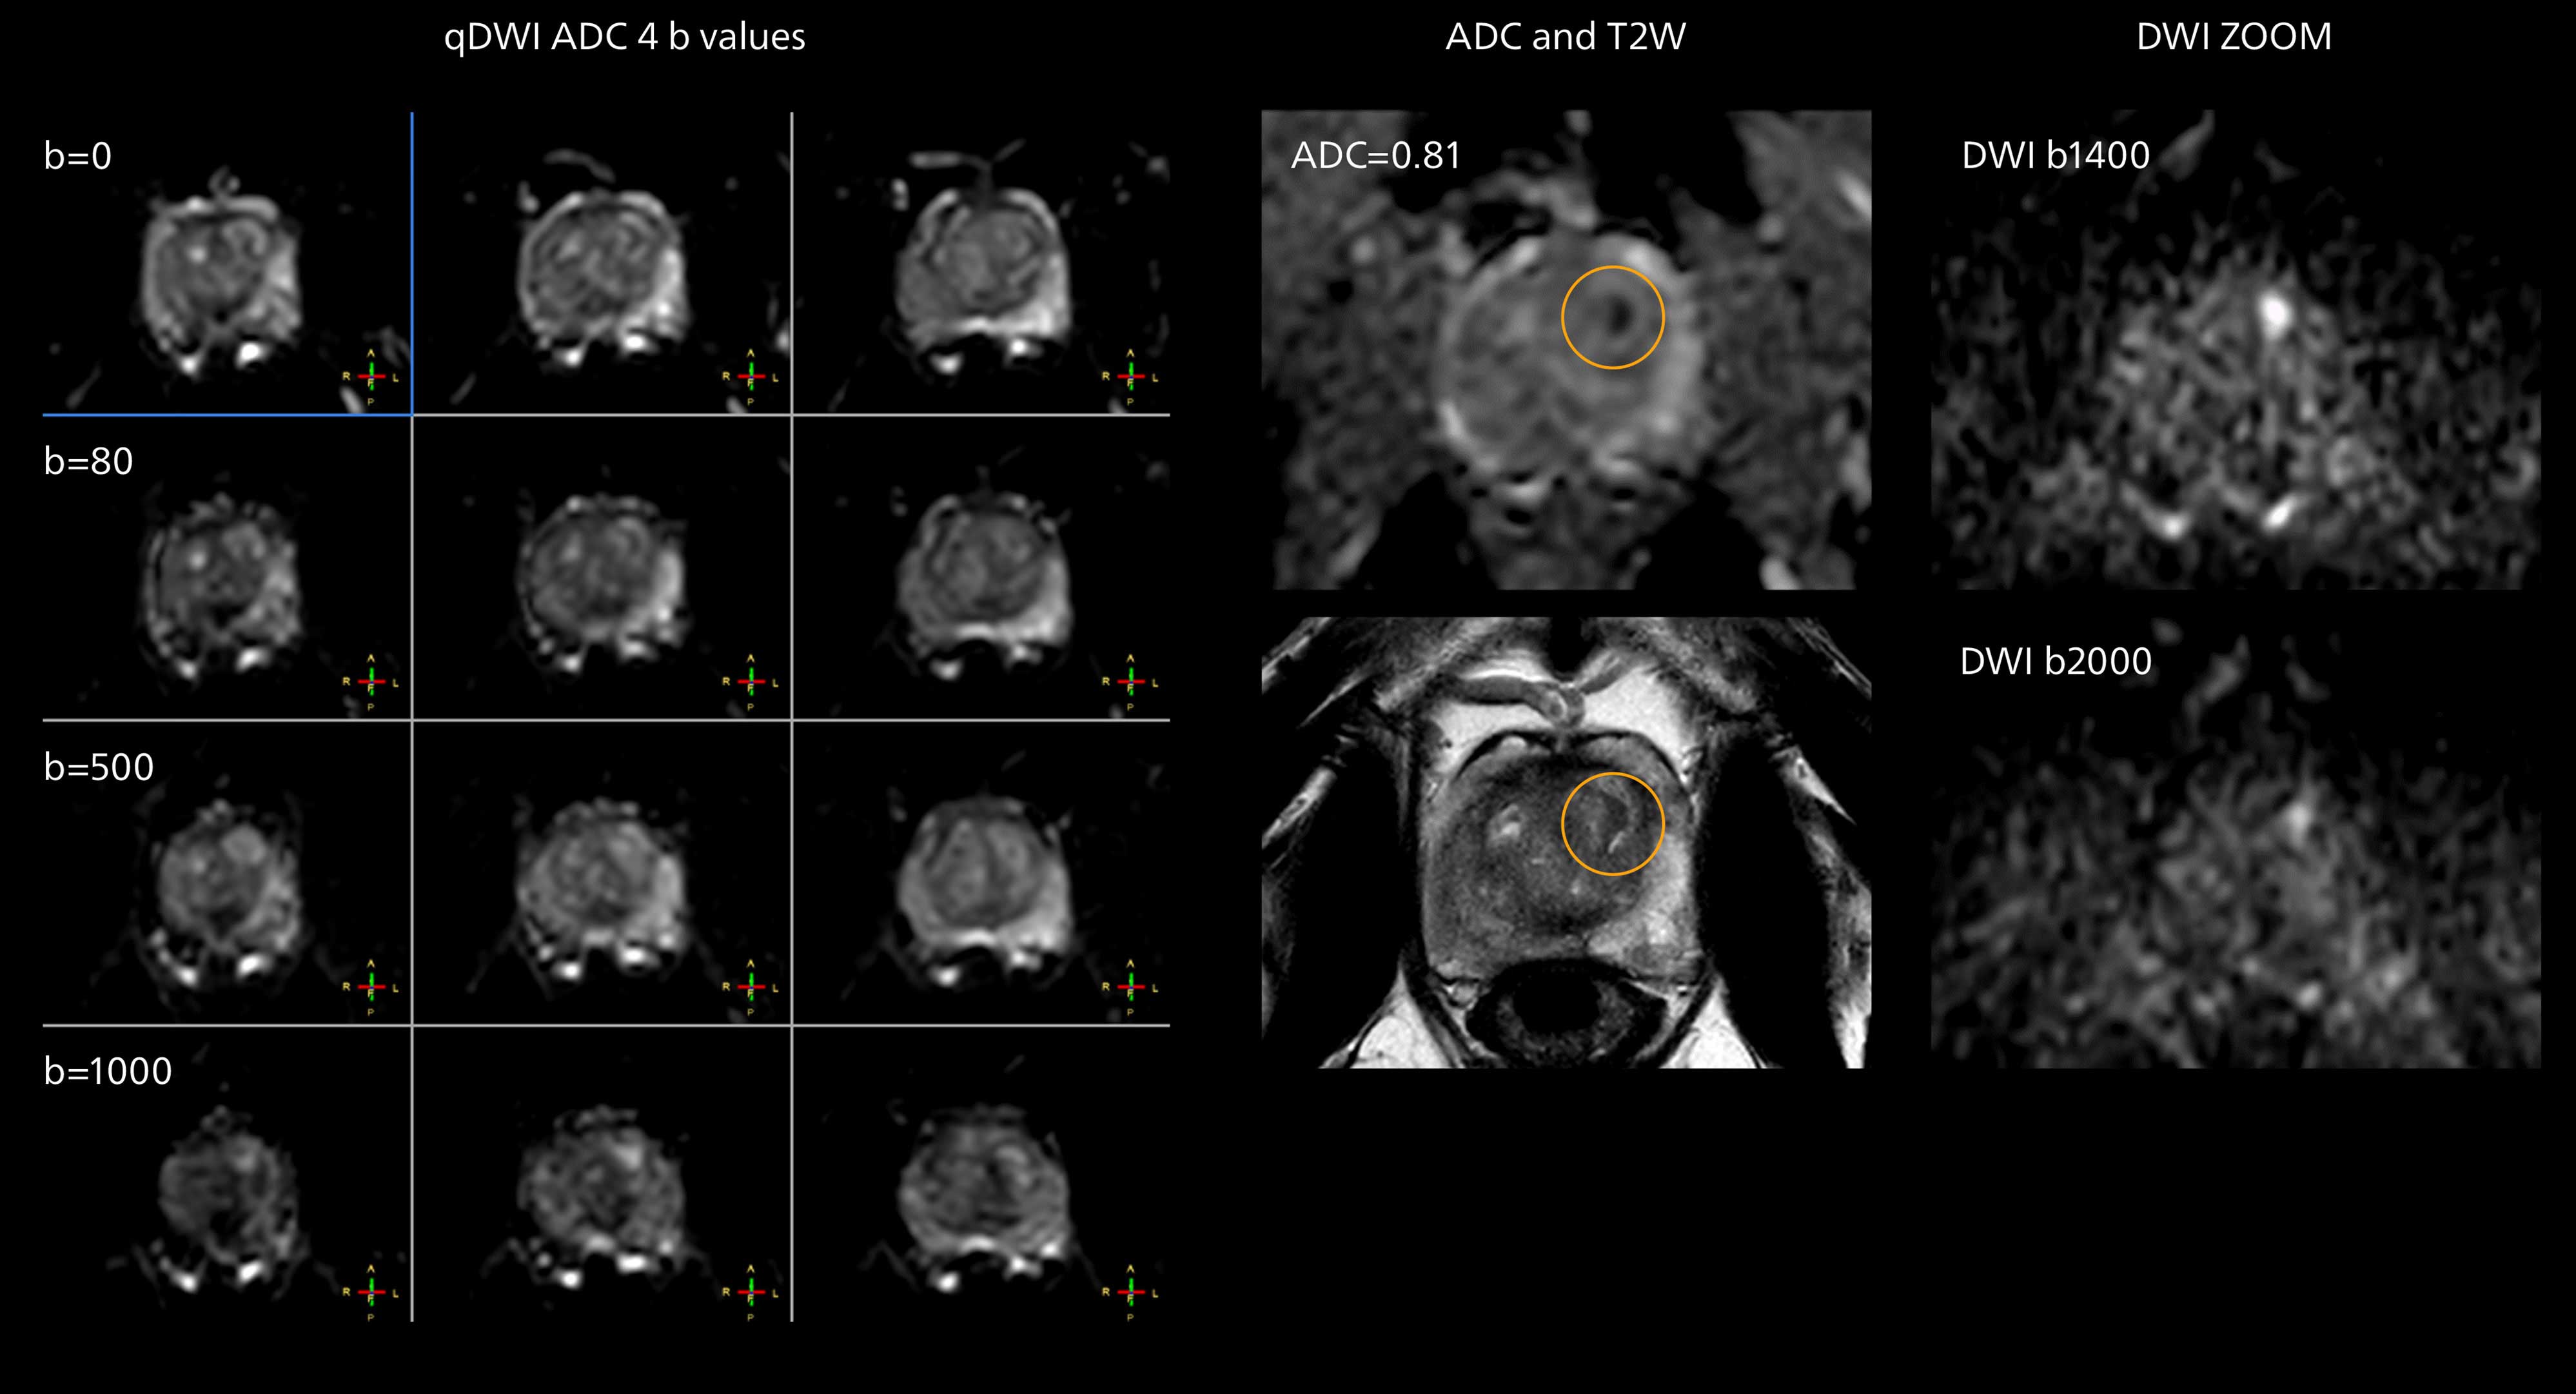

The prostate DWI done so far with the MR 7700 looks promising; the quality of visualizing the gland and the areas of disease seems significantly improved. “In one of our first prostate patients we were already able to acquire a quite high-resolution diffusion image – using a b-value of 3000 – that clearly delineated the prostate lesion. That was a very nice example of what the MR 7700 gradients can achieve,” he says.

Diffusion weighted MR imaging of prostate

Diffusion weighted imaging of prostate. Examples on the left show the regular clinical diffusion protocol with four b-values up to b1000 s/mm². On the right, the T2W image shows a hypointense lesion that has low ADC and is clearly visible in b1400 and b2000 diffusion images, suggesting malignancy.

In one of our first patients we were able to acquire a quite high-resolution diffusion image with a b-value of 3000, which clearly delineated the prostate lesion.